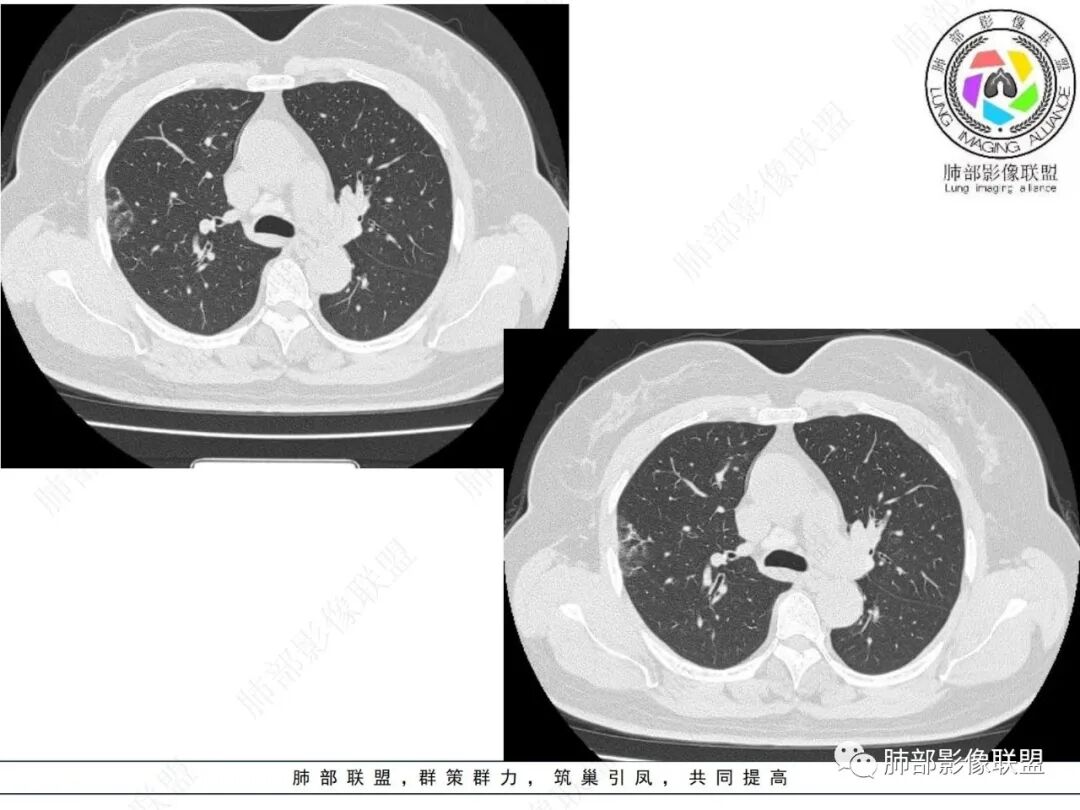

实性部分较密实,不规则,隐约见棘突或刺状突起,未见钙化、空洞或液化区,实性边缘可见斑状略低密度间隙(借用王兆宇老师课件,称其呈“松软”的形态)。动脉期实性部分较明显不均匀强化,如果有完整增强图,还可以观察内部血管情况。

纵隔窗相对肺窗病灶相对小,仅部分实性影呈现。病灶张力不高,相邻胸膜增厚(糊墙),未见明显胸膜牵拉凹陷。

右肺上叶胸膜下混合磨玻璃结节,磨玻璃部分与实性部分密度都不均匀,病灶有重力分布效应,小叶间隔阻挡,收缩力羸弱。中老年女性,如此大范围病灶,缺乏临床表现,会让人警惕非感染性病变,尤其是恶性病灶可能!

病灶磨玻璃部分边界较清楚,有重力分布趋势,可能会想到黏液腺癌,或者分泌粘液的腺癌的可能性。不支持地方也有,如实性部分密度偏高,病灶强化程度偏高等。

经验性抗炎治疗,病灶活检是较好的鉴别方式。单就影像而言,复查病灶进行性进展,沿支气管出现播散灶也是粘液腺癌诊断的有力证据。